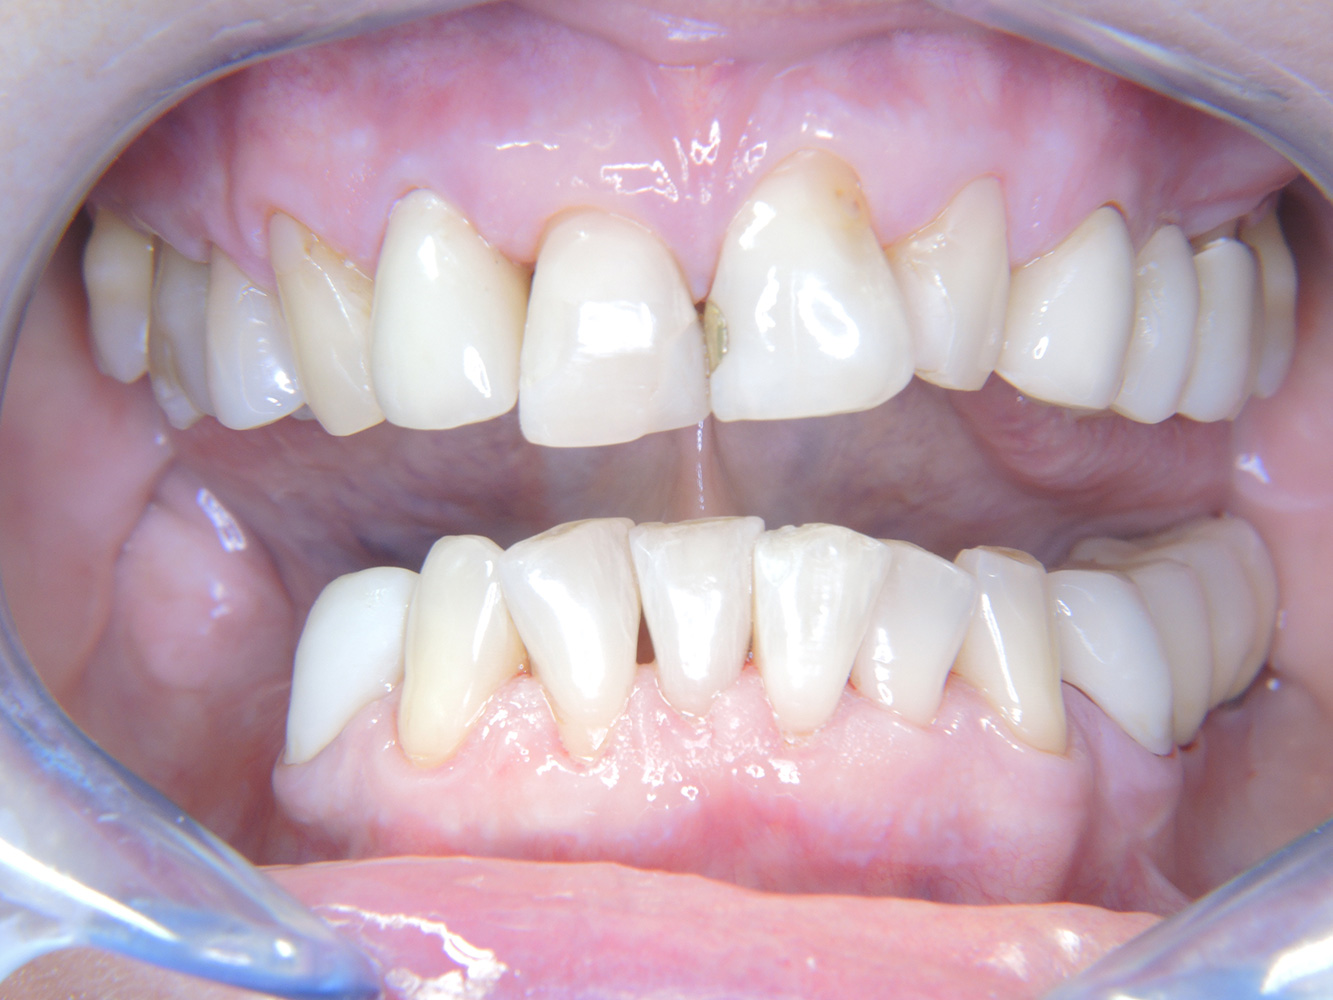

Die 68-jährige Patientin hat keine zahnmedizinisch relevanten allgemeingesundheitlichen Vorerkrankungen oder Medikation, auch aus dem Lebensstil ergibt sich kein besonderes Risiko. Die Patientin hat zwei Implantate (3. Quadrant, seit fünf Jahren) sowie eine parodontale Vorerkrankung (Parodontitis Stadium IV, Grad B) mit Zahnverlust. Derzeit zeigen sich stabile parodontale Verhältnisse. Für die Prophylaxesitzung ergeben sich vier Empfehlungen in den Bereichen Anamnese/Befund, Motivation/Instruktion, der Wahl der geeigneten Instrumente und für Resümee/Folgetermin.

Trotz der stabilen Verhältnisse sollten auch bei dieser Patientin die Motivation/Instruktion nicht vernachlässigt werden. Besonderes Augenmerk gilt dem Erlernen der richtigen Implantatpflege. Gerade hier kann eine gute häusliche Pflege einen wichtigen Anteil an der langfristigen Stabilisierung der Mund- und Implantatgesundheit haben.

In der Instrumentierung gilt im Bereich der Implantate eine besondere Vorgehensweise. Zum Erhalt der Implantatoberfläche bei gleichzeitig effektiver Reinigung ist die Wahl passender Pulver und Instrumente ausschlaggebend, wie etwa der gezielte Einsatz von Pulverstrahlgeräten mit speziellen Paro-Spitzen. Die Wahl des geeigneten Pulvers kann bedarfs- und risikogerecht erfolgen, beispielsweise kann neben dem passenden Abrasionsgrad auch auf diätische Anforderungen (u. a. zuckerfrei, salzarm) eingegangen werden.